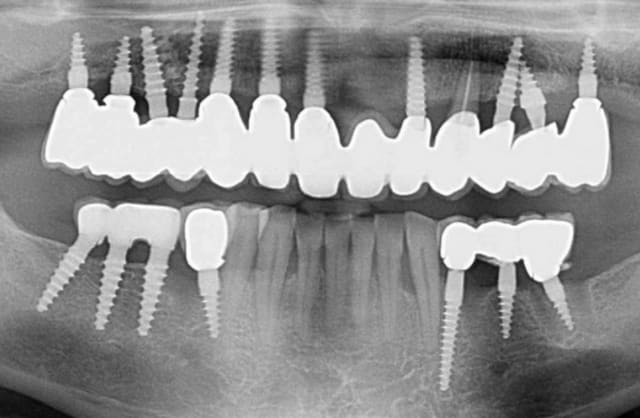

pour répondre à ta question : depuis 1994 , oui d ailleurs dans un des cas présentés tu as une radio après 10 ans :-)! (46 47 )

Si je comprends bien on ne peut poser tes implants si on a les dents en place au préalable ...En postérieur c'est léger , les dents étaient absentes lorsque tu as vu ce patient ?

De l'intérêt de garder une dent en secteur 2 ?

Il y a des proximités pour le moins surprenantes .

Des absences d'implants dans certaines zones également .

J'en reviens au premièrement , tu ne mets des implants qu'après extraction , donc on t'enverra des patients avec les dents ...

bonne question :-)

garder une dent en "connexion" avec les implants car en laissant une dent naturelle , le patient peut garder une sensation et mieux contrôler ses forces masticatoires. Donc lorsque c est possible je préfère garder une dent.

je ne me mets pas des implants qu après extraction, ici c est le cas puisque c est une implantation immédiate,mais cette technique est aussi utilisée sur les sites édentés.